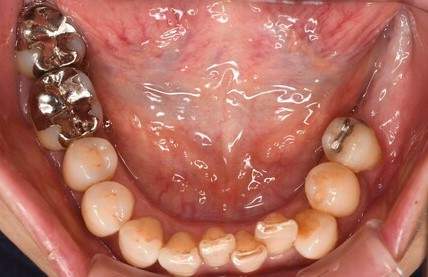

口腔内写真-1

口腔内写真-2

- Befor

- After

口腔内写真-3

| 年齢 | 60代・男性 |

|---|---|

| 主訴 | 左上5番6番 |

| 治療内容 | インプラント埋入 |

| 治療費 | インプラント埋入料 825,000円 ソケットリフト(骨造成) 220,000円 サージカルガイド 66,000円 2次OPE 44,000円 静脈内鎮静麻酔 77,000円 合計 1,232,000円 (2024年1月現在) |

| 治療期間 | 10ヶ月 |

| リスク・副作用 | リスク・副作用 |

| 治療方針 | 左上5番6番目の歯根破折の為抜歯を行いました。その後インプラント埋入を行いました。 |

| 特記事項 | インプラントは人工物なので虫歯になることはありませんが、歯周病(インプラント周囲炎)にはなります。 インプラントを長持ちさせるには、毎日の歯磨きと合わせて、3〜6ヶ月ごとの定期検診でのクリーニングが大切です。 |

| 担当者所見 | 歯を失ったまま放置してしまうと、周囲の歯に負担がかかるため、お口の中全体のバランスが崩れます。 インプラントは、骨に人工の歯根を埋め、被せ物を被せる治療法です。 外科的な手術が必要ですが、健康な歯を削ることなく、天然の歯と同じようにかめるようになります。 |